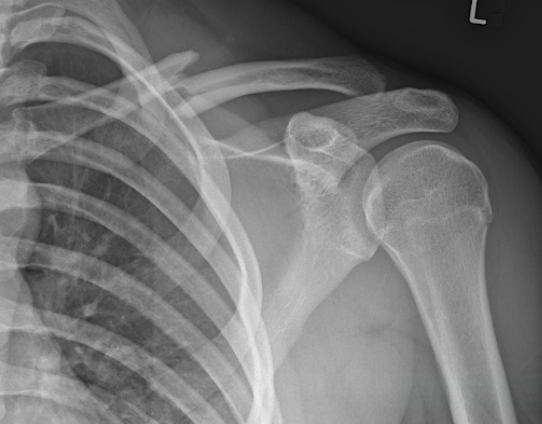

Shoulder Check: A common skier's shoulder injury

A 38-year-old female presents to the ski clinic for left shoulder pain after a fall while skiing. Her ski caught an edge causing her to fall directly onto her left shoulder. She now has significant pain in the left shoulder that increases with attempt at forward flexion and adduction at the shoulder. She denies any other associated symptoms.